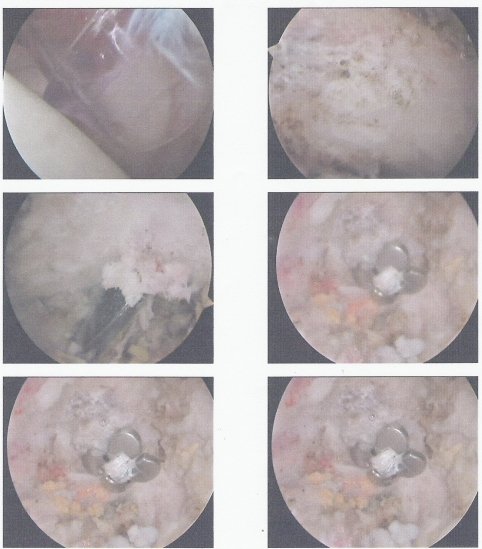

Bild1 mit Muskelgewebe, Bild2 nach entfernung des Muskelgewebes, Bild3 beim durchbohren des Schultergelenks mit 4mm Bohrer, Bild4,5,6 nach richtig Plazierung der Klavikula mittels TightRope-System.